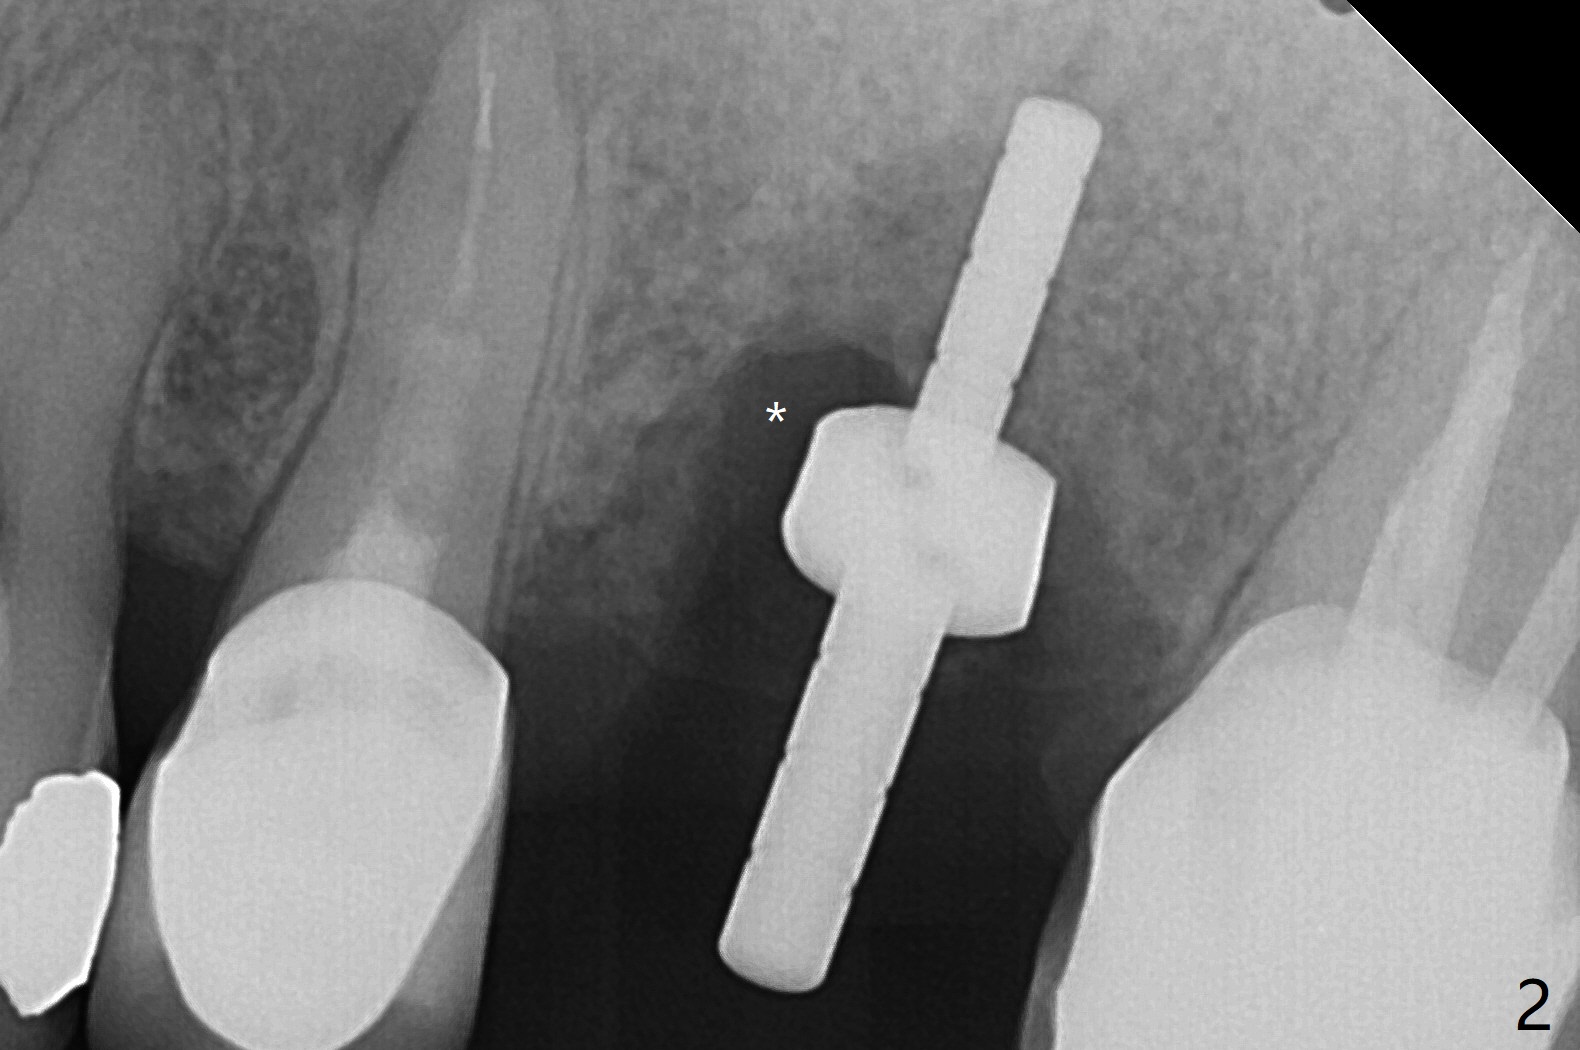

左上6腭侧退缩牙龈(图一:箭头)深部没有骨壁(图二:*),4.5x11毫米植体周围缺损(图三:*)由粘性骨粉(皮质骨,图四:*)填入,即刻临时牙冠(图五:P)覆盖腭侧缺损(空箭头)和PRF膜。临时牙冠颊腭侧做的很宽(图六),目的是关闭腭侧缺损,术后四周在不影响骨粉覆盖情况下,牙冠腭侧适当向颊侧缩小(图七:箭头),但是不应该缩短龈下边缘。术后四个月骨粉形态接近原位骨(图八),但是腭侧软硬组织仍有缺损,炎症。